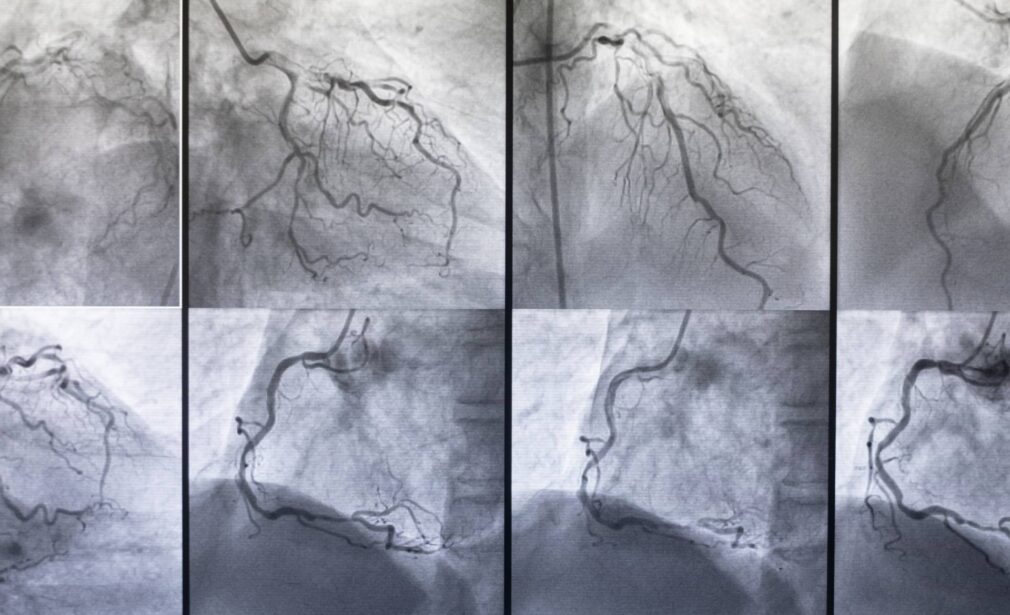

Coronary Angiography is a specialized diagnostic test used to visualize the blood vessels of the heart (coronary arteries). This procedure helps identify blockages, narrowing, or abnormalities that may be restricting blood flow.

During the procedure, a thin catheter is inserted—usually through the wrist (radial artery) or groin (femoral artery)—and guided to the coronary arteries. A special contrast dye is injected, and X-ray imaging captures detailed pictures of the arteries, allowing Dr. Sharma to assess the condition of the heart’s blood vessels.

X-ray imaging to identify blockages